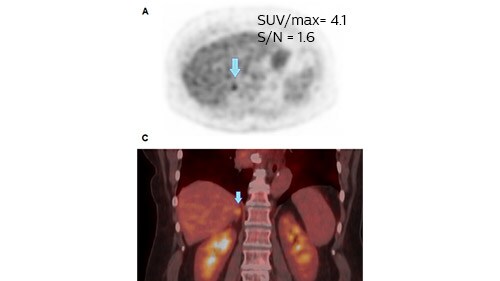

Case study of metastatic adrenal gland

Clinicians at Isala also recently published a case study² that reported results from a scan of a 68 year-old woman suspected of lung cancer, who underwent a whole body FDG-PET scan.

Figure 1: The 4 mm voxel reconstruction shows no enlargement of the gland in CT and a slightly increased FDG uptake. The gland was considered benign and combined chemotherapy was initiated.

Figure 1: The 2 mm voxel reconstruction showed a higher SUVmax and a higher contrast despite increased noise. The gland was considered suspicious and more likely to be metastatic.